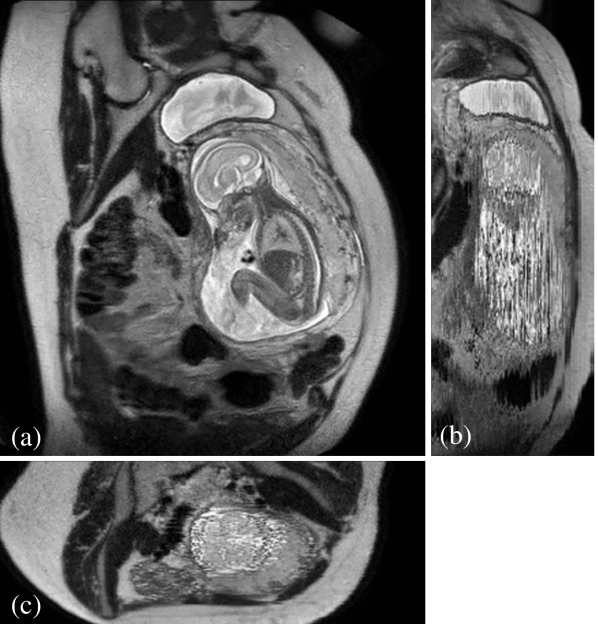

During image acquisition the fetus is not sedated and moves freely as well as the mother breathes normally. As a result, movements are likely to corrupt the scans, hiding pathology and causing overlap between different anatomical regions. In order to limit these artifacts, fast scanning sequences such as ssFSE [10] allow for the rapid acquisition of single slices at high in-plane resolution in a large field of view and good tissue contrast of the uterus. However, when acquiring a 3D volume through a stack of slices, inter-slice artifacts in the out-of-plane views are highly likely. Consequently, this restricts reliable diagnostics to individual slices in the current clinical practice. Fig. 1 depicts a typical example of motion related artifacts in a fetal single-shot fast spin echo (ssFSE) scan. The observed motion (c.f. Fig. 1 b & c) is of unpredictable nature and consists of a combination of maternal respiration movements, fetal movements and bowel movements.